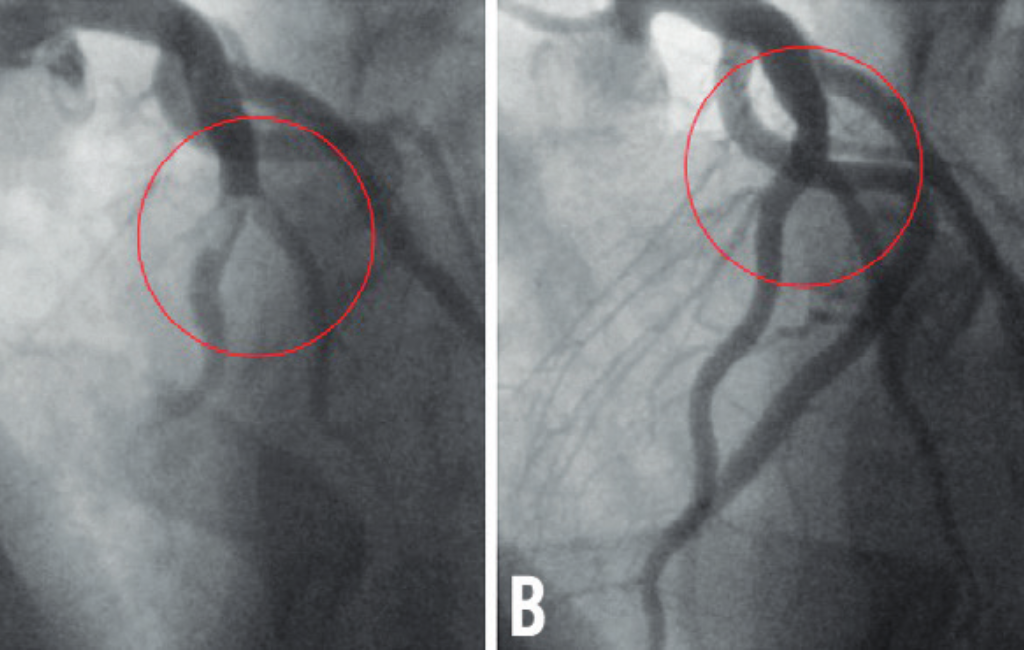

Angioplasty & Stent Placement – Restoring Blood Flow to the Heart

• Balloon Angioplasty & Stenting – Non-surgical, quick recovery treatment for heart blockages.

• Drug-Eluting & Bioabsorbable Stents – Advanced solutions for artery widening.

Before & After

Cardic Surgery Results